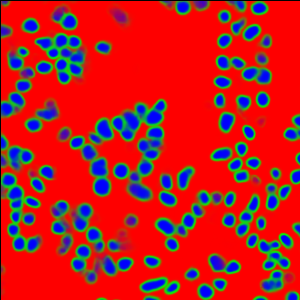

The task of nuclei segmentation can be roughly divided into two stages: the first stage is extracting the foreground(nuclei), the second stage is segmenting the connected foreground area into separated nuclei and finding out the boundary of each nucleus. Our method intends to merge these two steps by extracting the nuclei and their edges at the same time. That is the reason why it is named ”nuclei-boundary(NB) model”. As shown in Fig.3, the output of the NB model has three channels, each has the same height and width with the input image. Its values represent the probabilities of each pixel being , or class, respectively. The manual annotation for our segmentation problem is the boundary of each nucleus. A pixel belonging to the class means that it is on or inside an annotated boundary and within 2 pixel from the boundary. Pixels of the class are those that are inside annotated boundary but are not pixels. Correspondingly, the output can be regarded as an RGB image and the estimated maps of the , and are represented by red, green and blue, respectively, as shown in Fig.3. To generate the ternary mask for training, we apply a morphology operator to each nucleus to obtain the pixels, and then subtract pixels from the nucleus to get pixels.

II-C5 Post-processing

From Fig.6, we can see that the raw prediction results already show clear nucleus areas and boundaries. Due to this reliable prediction results, we no longer need the complex region growing algorithms [22, 17] and splitting algorithms [27] to extract the final segmented areas. These methods usually strongly rely on manual parameter tuning to get good performance and is computationally demanding. Instead, we use a parameter-free postprocessing procedure that runs in a negligibly short time. Since our NB model detects both and classes, all we need is the class map. Then the class map is transformed to a binary map using a constant threshold . In this way, each connected component in the binary image indicates the area of one nucleus. At the end, in order to recover the shape, we can simply apply the dilation operation to each connected component.

Figure 6 shows how our method segments the nuclei step by step. The color variety is well controlled by the color normalization procedure. The prediction result shows clear nuclear areas and nucleus boundaries. In the final segmentation result and ground truth image, each nucleus is represented by a different color.